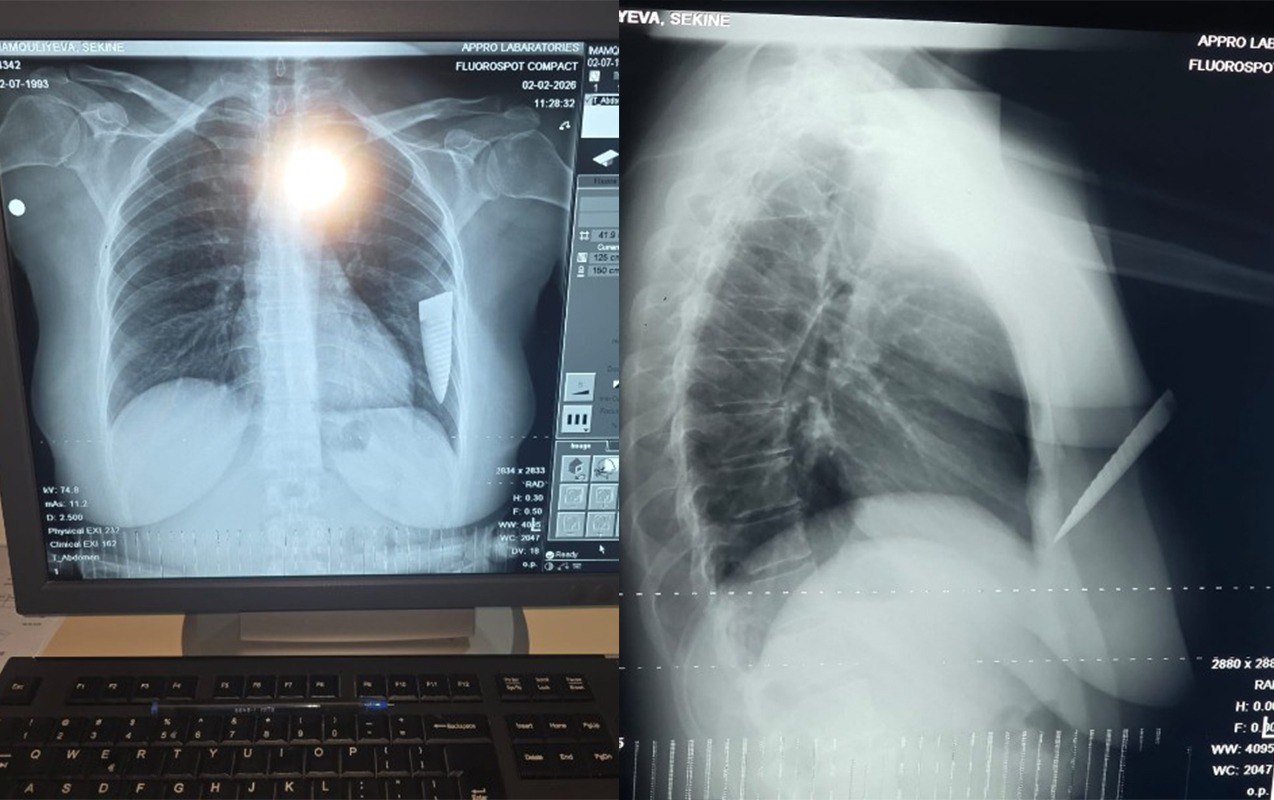

“Hadisə fevralın 1-də saat 19:00 radələrində yaşadığım Gəncə şəhərindən Şəmkirə dəvət edildiyim toy mərasimindən çıxarkən baş verdi. Şadlıq evinin qarşısında maşınıma minərkən əvvəllər qeyri-rəsmi münasibətdə yaşadığım Əli Kamran oğlu Əsgərov qəfil hücum etdi. O, gözlənilmədən maşınıma yaxınlaşdı, sağ ön qapını açaraq boğazımdan tutub boğmağa çalışdı. Daha sonra cibindən bıçaq çıxarıb 4 dəfə zərbə endirdi. Zərbələrdən biri ürək nahiyəmə, üçü isə sol qoluma dəydi. Həmin vaxt bıçaq qırılaraq döş qəfəsimdə qaldı, yoxsa daha çox zərbə endirib məni öldürə də bilərdi, çünki bıçaqla ardıcıl olaraq məni vururdu. Bıçağın qırıldığını, ətrafdakı insanların səs-küyə gəldiyini görərək qaçıb getdi”, - şikayətçi bildirib.

S.İmamquliyeva qeyd edib ki, hadisəyə onun sevgilisindən ayrılması səbəb olub: “Artıq münasibətimiz bitmişdi. Əli Əsgərov ayrılıqdan sonra məni mütəmadi izləyir, hədə-qorxu gəlirdi. Məni bıçaqlayandan sonra Şəmkir Rayon Mərkəzi Xəstəxanasına, oradan isə Gəncə Beynəlxalq Xəstəxanasına aparılaraq əməliyyat olundum. Döş qəfəsimdə qırılıb qalan bıçağın kəsici hissəsi əməliyyatla bədənimdən xaric edildi. Hazırda səhhətimdə yaranmış ağır fəsadlar səbəbindən işləyə bilmirəm. Bu hadisəyə görə külli miqdarda maddi-mənəvi zərərlə üzləşmişəm, qarşı tərəf isə heç maraqlanmır. Hadisəni törədən şəxsin saxlanıldığı bildirilsə də, istintaqın gedişindən də məlumatsızam. Qarşı tərəf imkanlıdır və təsir imkanları çoxdur.